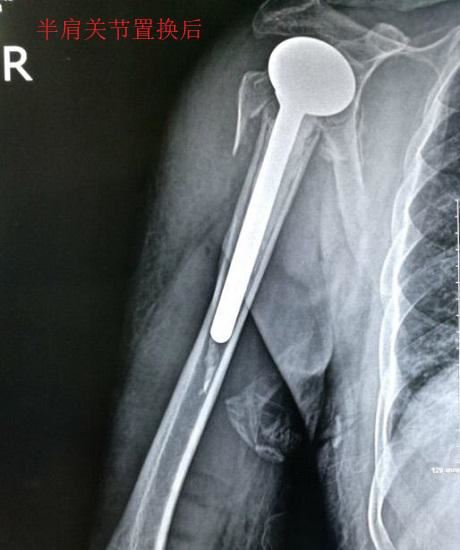

1、治疗手段。人工肩关节置换是指:用人工假体替代肱骨头或(和)盂肱窝,以获得较好的肩关节运动能力,多用于肱骨头部位的骨折。人工肩关节置换有全肩关节置换(替换盂肱窝和肱骨头)和肱骨头置换术(只替换肱骨头)之分,另外还有反置式全肩关节置换术(全肩关节替换,但将肱骨头和盂肱窝换位置)。无论哪种形式的人工肩关节置换术,都涉及大范围的软组织切开,对术后康复过程也有较高要求,但往往不能获得完全的肩关节功能。2、适应证??悸堑饺斯ぜ绻亟谥没?#x778899;术切口大、康复要求高、功能有限等方面的原因,多用于较为复杂和严重的肱骨头骨折(例如:肱骨粉碎性骨折合并盂肱关节脱位,高龄或重度骨质疏松者的肱骨头骨折,肱骨头缺血性坏死等传统手术方法无效者)。